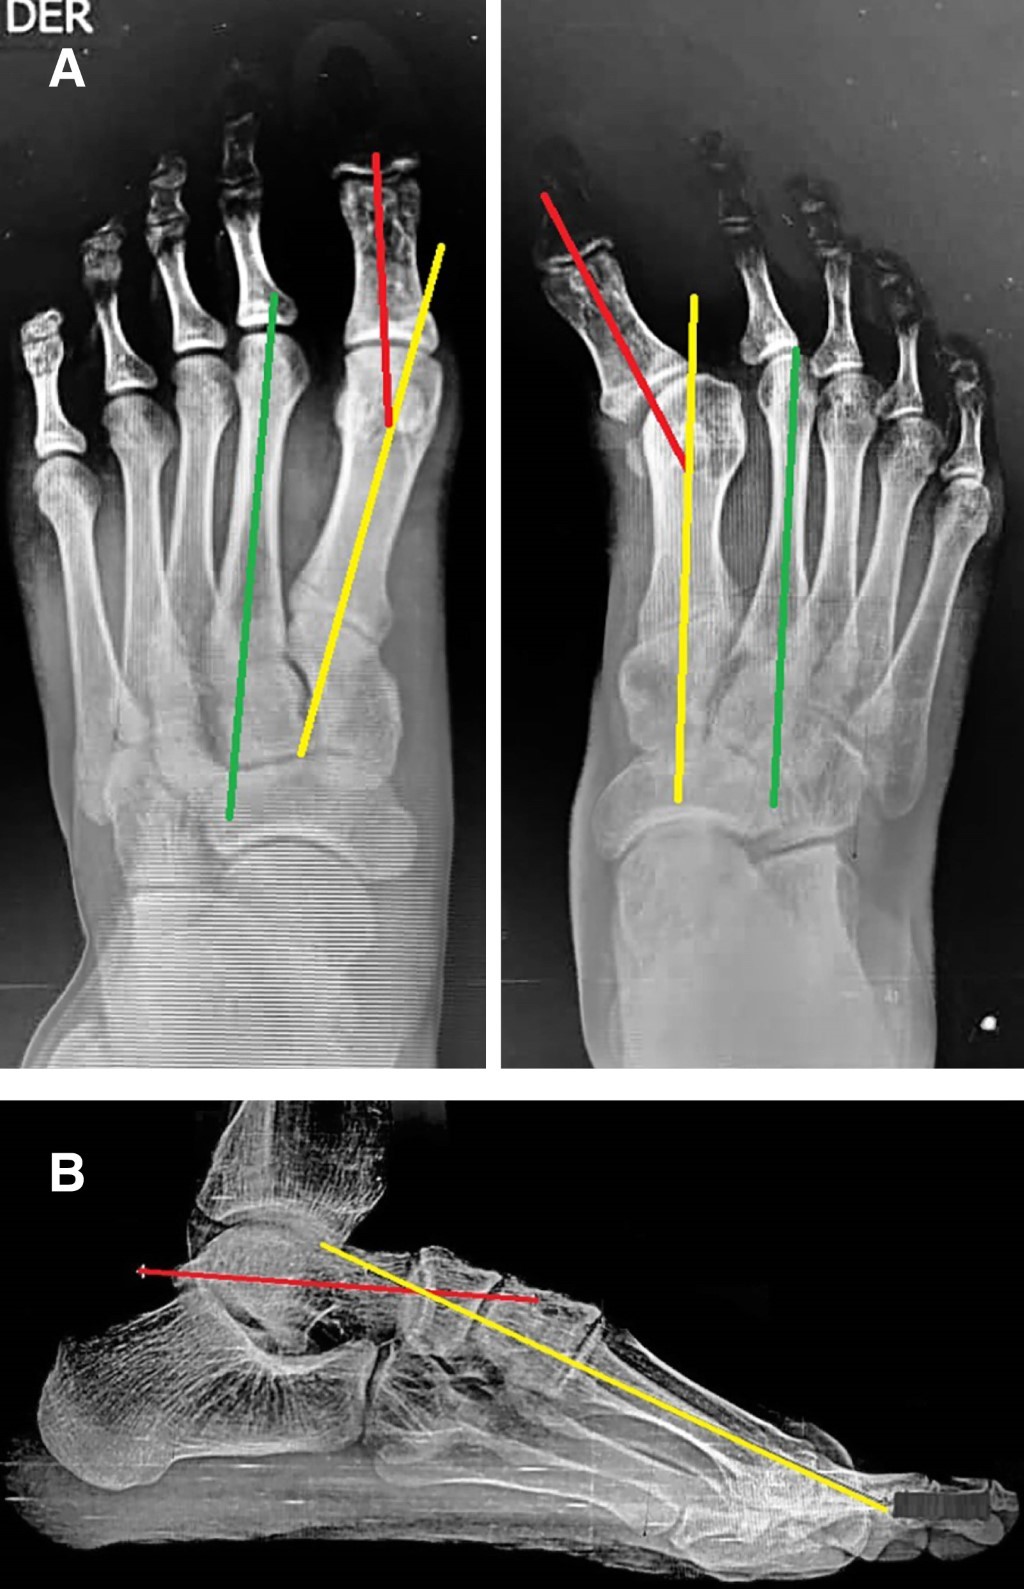

From congenital talipes equinovarus to hallux varus: a rare complication of the extended posterior internal release technique

Introduction: congenital talipes equinovarus (CTEV) is a highly prevalent deformity that affects patient functionality. Even with adequate treatment, overcorrection can result in deformities such as hallux alterations. The most common deformity in this context is hallux flexus, or dorsal bunion; however, we present a case of hallux varus as a complication not previously reported in the secondary literature secondary to the management of CTEV. Case presentation: a 17-year-old patient with a history of CTEV was treated with a posterior internal release (PIR) at five years of age. He presents with left hallux varus with significant functional impairment. Soft tissue release and transfer of the abductor hallucis and extensor hallucis longus tendons are proposed. During follow-up, adequate maintenance of the deformity correction is evident with no recurrence at 18 months. Conclusion: hallux varus after PIR in CTEV is an unusual complication, whose etiology lies in persistent contracture or fibrosis of the adjacent capsuloligamentous and musculotendinous structures. Treatment should address the various dynamic and static alterations through specific soft tissue releases, tendon transfers, or arthrodesis. In patients with flexible hallux valgus, restoring muscle balance may be sufficient to correct the deformity and prevent recurrence.

Figure 1

Figure 2

Figure 3

Figure 4

Figure 5

Figure 6

Figure 7